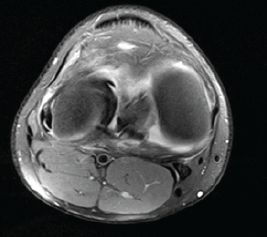

Simultaneous Anterior Cruciate Ligament Avulsion Fracture with Bilateral Posterior Meniscal Root Tears of the Knee: A Case Report

Deem Alsedais , Bader Majed Aljadaan , Hamad H Aldakhil Allah , Abdullah Adel Al-Nasser , Ibrahim Ababtain ………………………………p.222-226